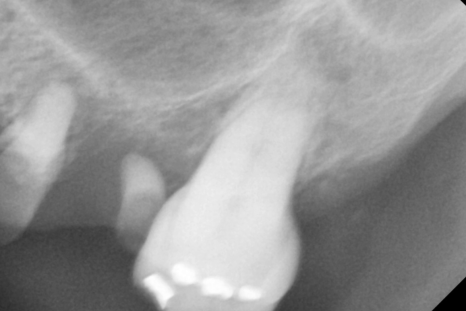

그래서 치아 뿌리 상태를 확인하는

작은 x-ray도 찍고

평가하였습니다.